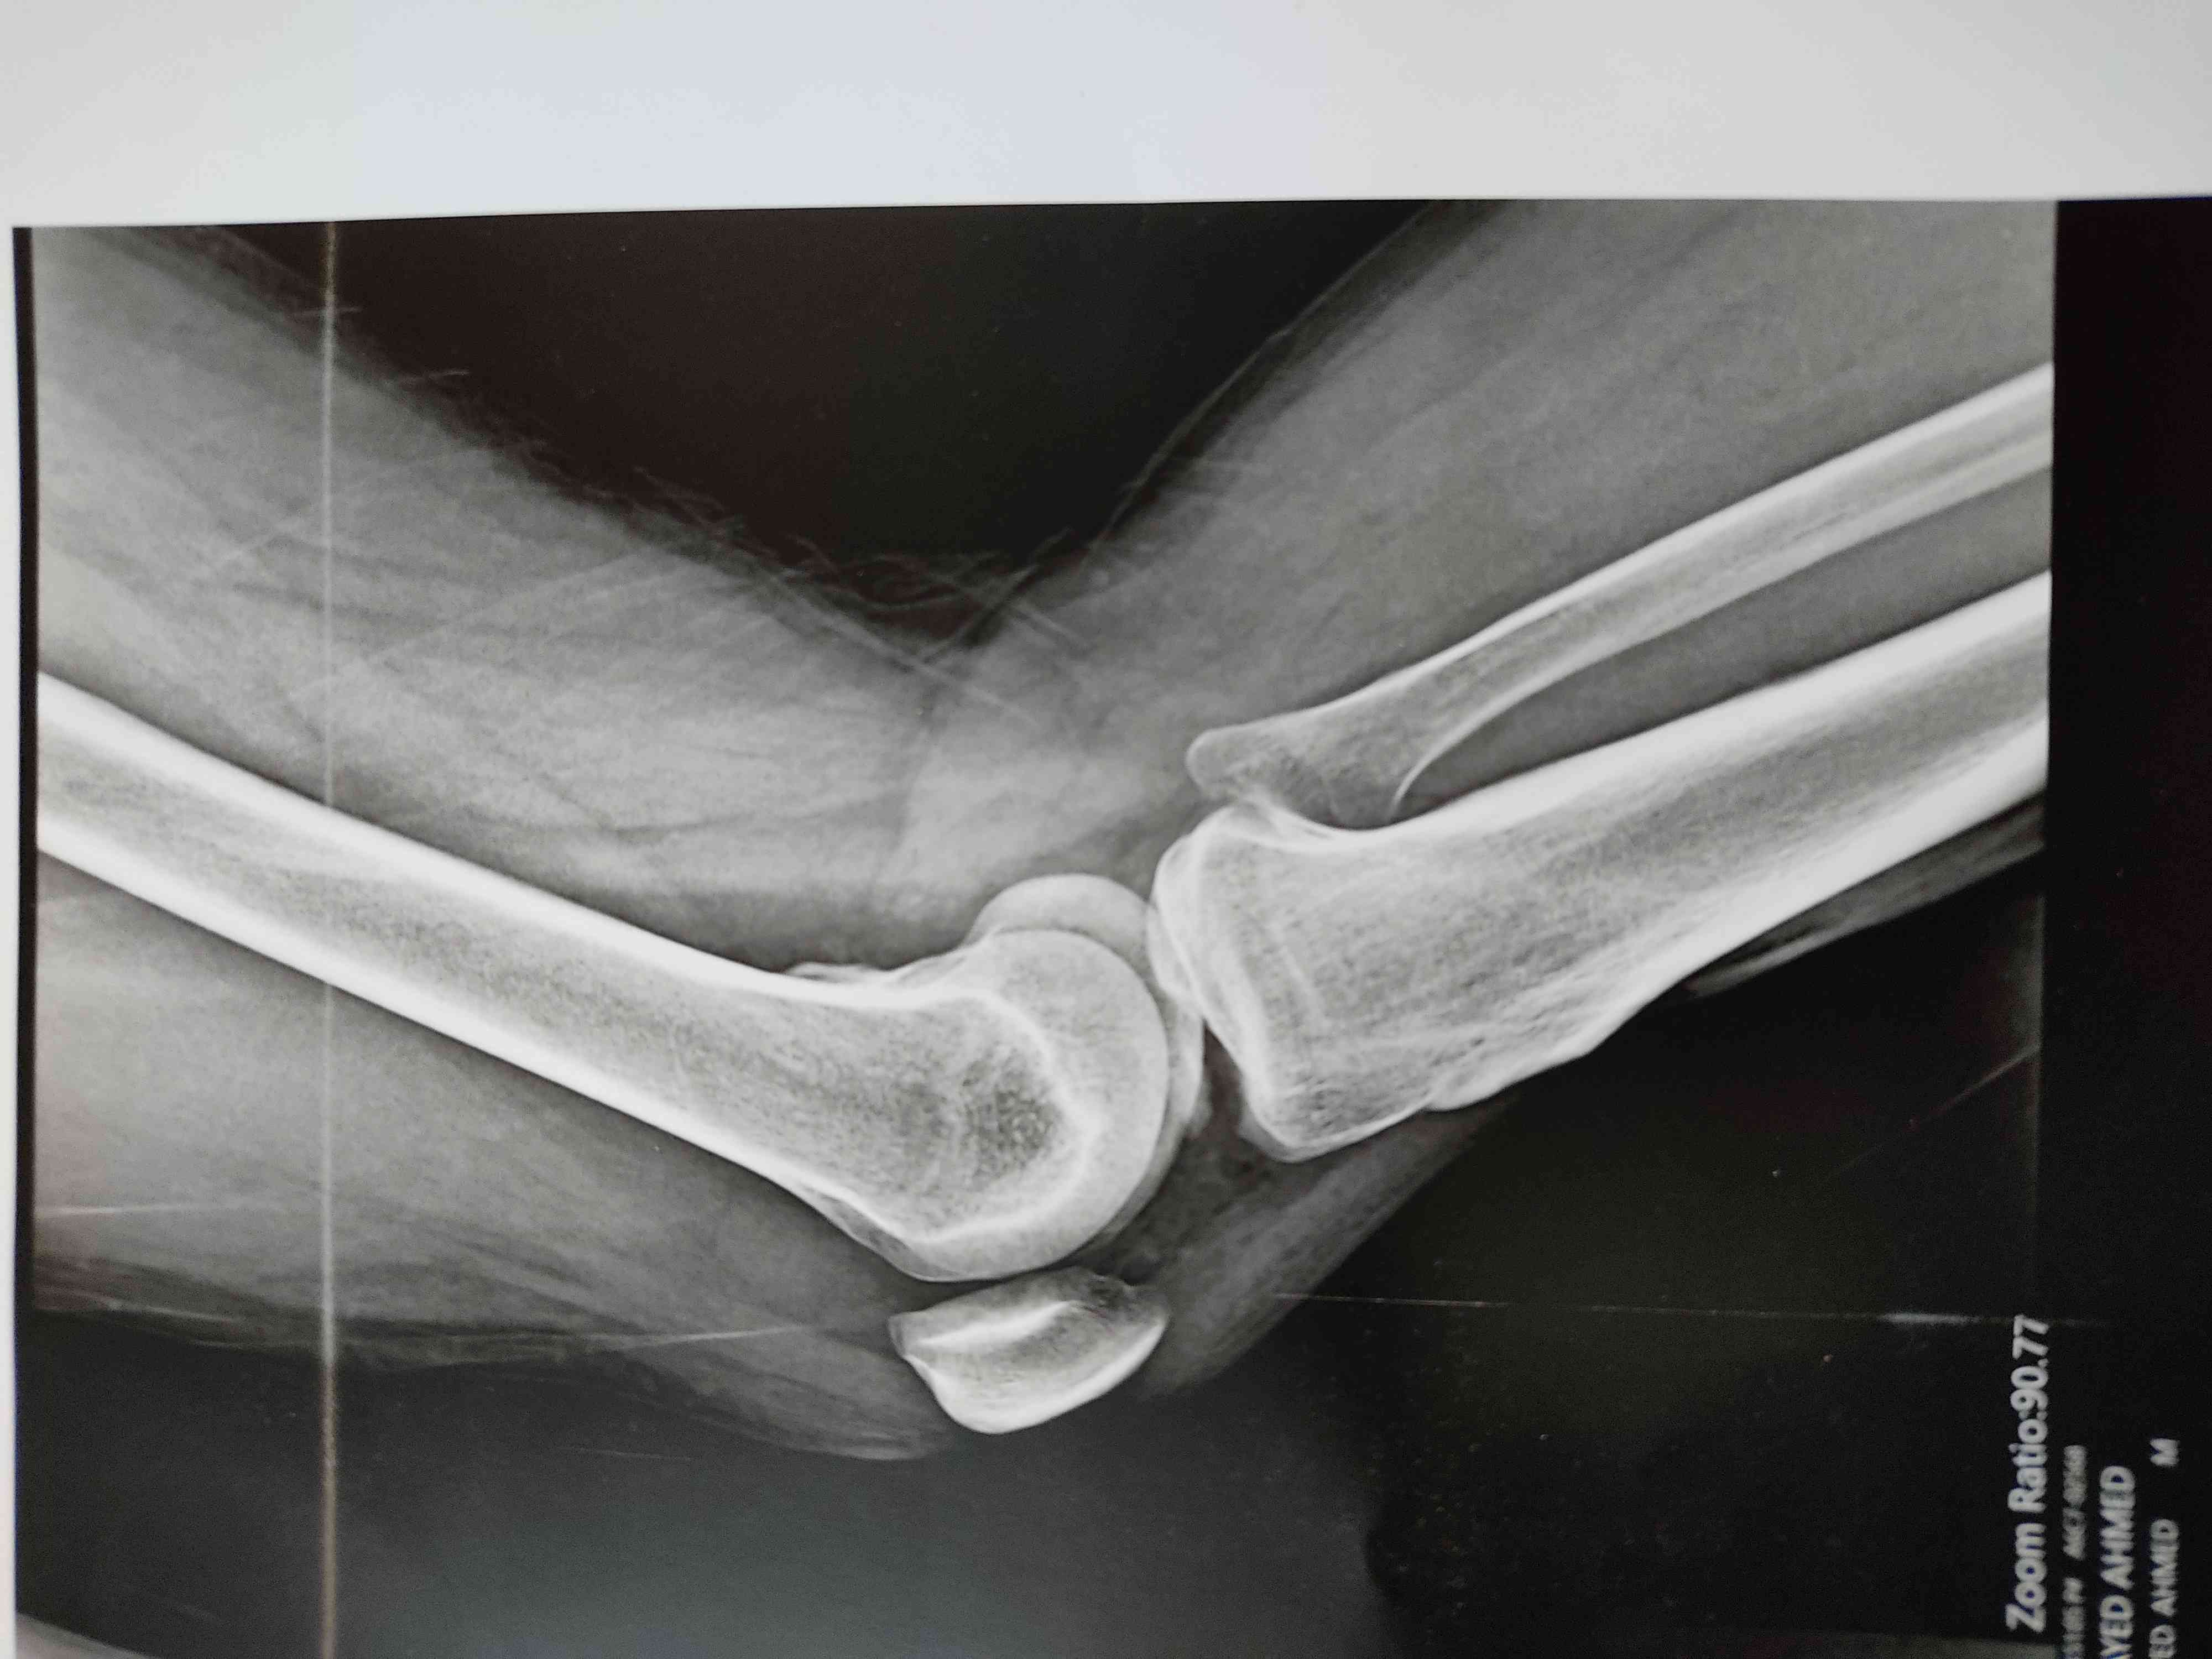

الم وغزة بالركبة نتيجة تصادم